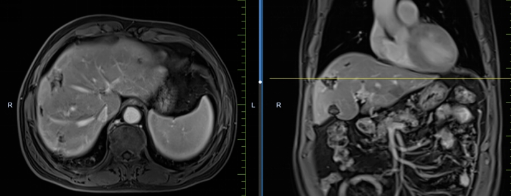

患者馬某某,男,60歲,因腹部不適行胃鏡及腹部CT,提示胃癌、多發(fā)淋巴結轉移、肝轉移,胃部病灶大小約11*6cm,淋巴結最大病灶約6*3cm,肝臟病灶最大約8.8*7cm。經(jīng)6周期化療+免疫,聯(lián)合中醫(yī)中藥后,病灶明顯縮小,進入維持治療階段,身體狀況與常人無異。

治療前

治療后